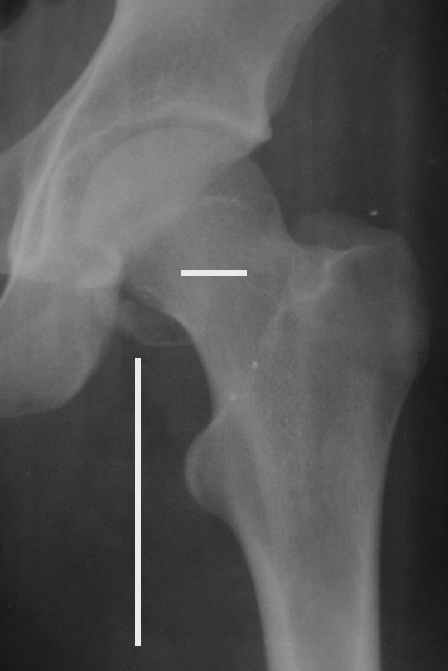

Уважаемые коллеги! Заканчивая обследование больного с переломо-вывихом бедра сделал ему обычные R-томограммы. Кажется удалось "поймать" и отломок и донорское место. Мои выводы - в скиаграмме. Считаю, что это передне-нижний фрагмент головки, образовавшийся вследствии отрывного перелома. На томограммах отломок обозначаю длинной стрелкой, а место откуда он оторвался - более короткой. Учитывая тот факт, что его размеры по КТ 25 х 15 мм считаю, что его фиксация на место необходима для профилактики артроза, что при 16-ти летнем возрасте пациента важно в плане максимального отодвигания эндопротезирования. Планирую оперировать его 24.05.05 г. Результаты представлю.

Прямой 19.05